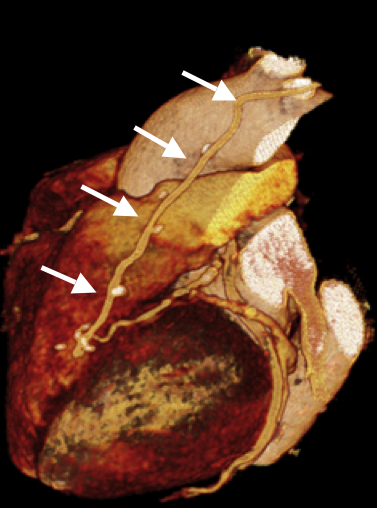

© Universitätsklinik für Radiologie und Nuklearmedizin

Die Abbildung zeigt eine CT Angiographie der Herzkranzarterien bei einer 77-jährigen Patientin, bei der ein Zustand nach Anlage eines LIMA-ad-LAD-Bypasses vor einem Jahr besteht. Die Patientin leidet unter neuerlichen Angina pectoris-Beschwerden.

Der Bypass ist regulär dargestellt (Pfeile), allerdings ist das Zielgefäß (distale LAD) nur sehr zart.